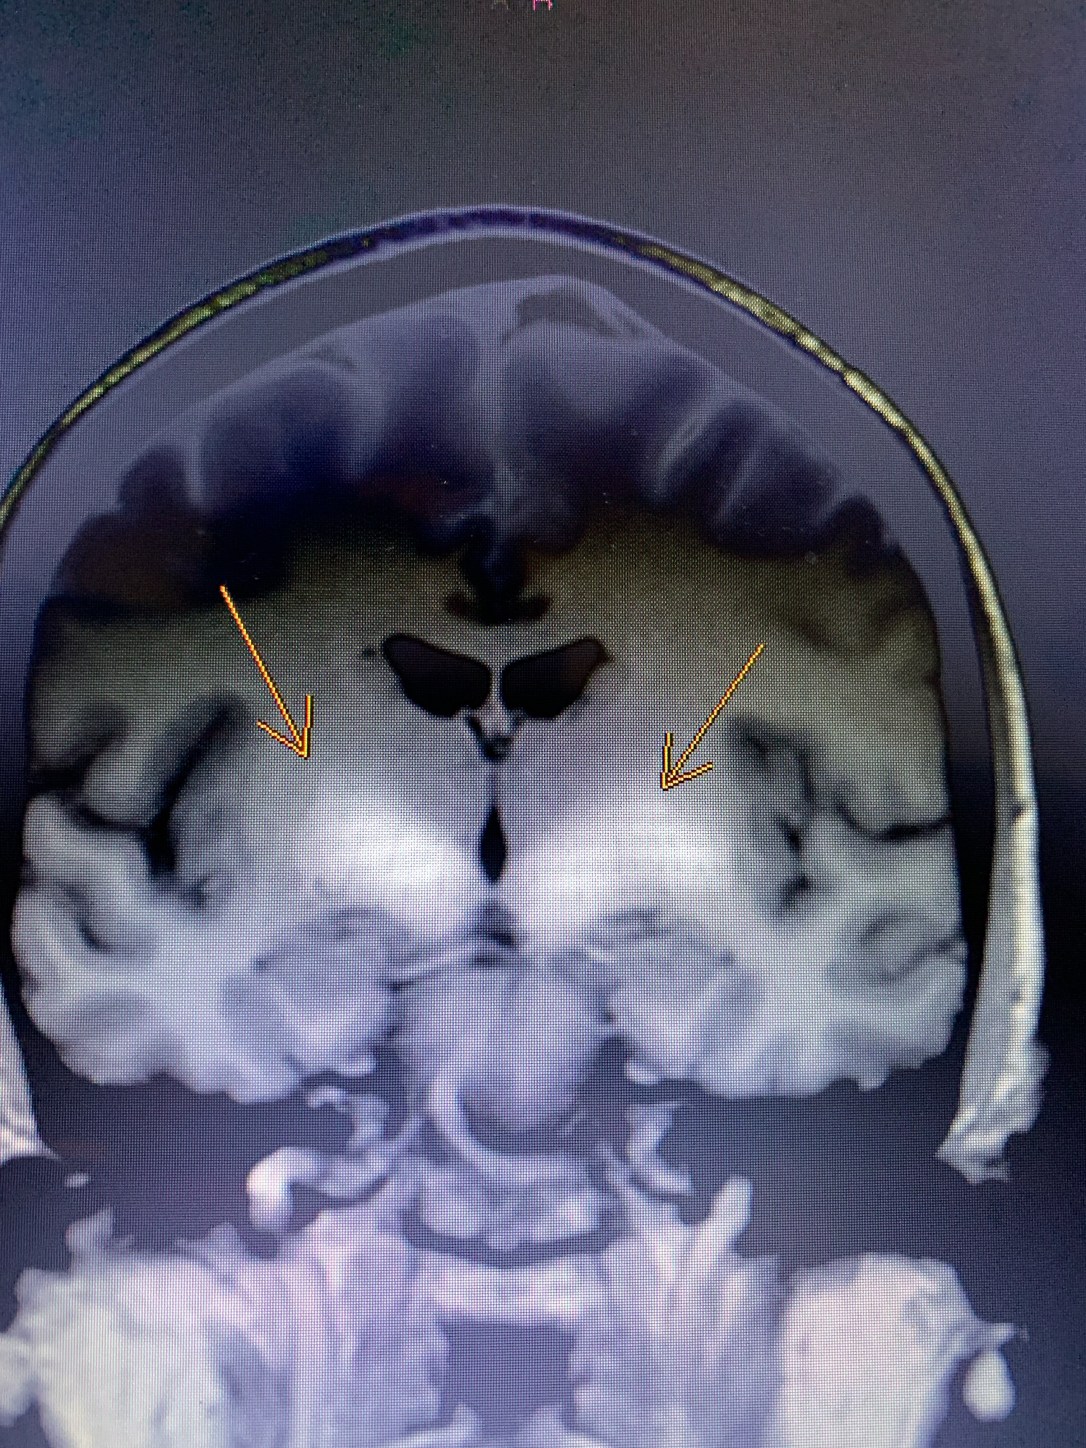

It’s been a frightening journey at times, especially with the unknowns, but we are beginning to have some clarity. A recent brain MRI showed significant damage to my brain stem, and basal ganglia, which are responsible for many of the automatic functions of the body. This information shed light on why I was having symptoms related to that area of the brain, like trouble regulating my breathing. All of these pieces started to fit together and pointed to Multiple System Atrophy. In some ways this was a relief, as the contenders like ALS have a very short length of survivability. MSA comes with its own fatal prognosis though, typically within 5-15 years. Being at year six, I already feel blessed for the time I’ve had and continue to enjoy. I’ve tried to stay in the moment and be continually grateful, although I’ll admit that sometimes my attitude stinks and I fall into a grumpy state of forgetting the gifts I’ve been given.